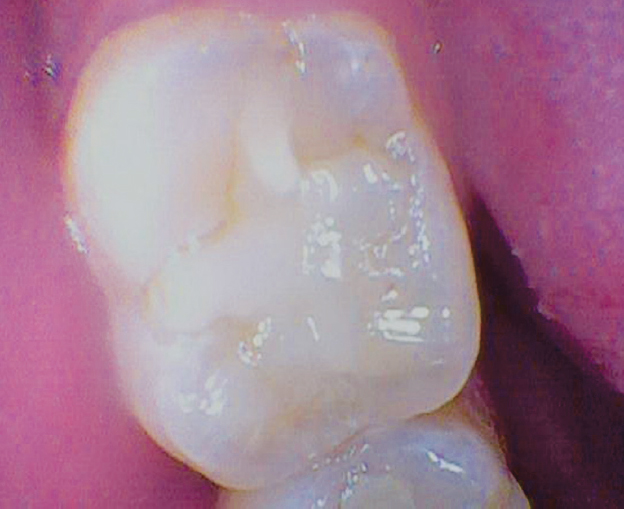

Fig. 7. Tooth 1.6 after 6 months, Black class I, clinically acceptable

Рис. 7. Зуб 1.6 через 6 мес., I класс по Блэку, клинически приемлемо